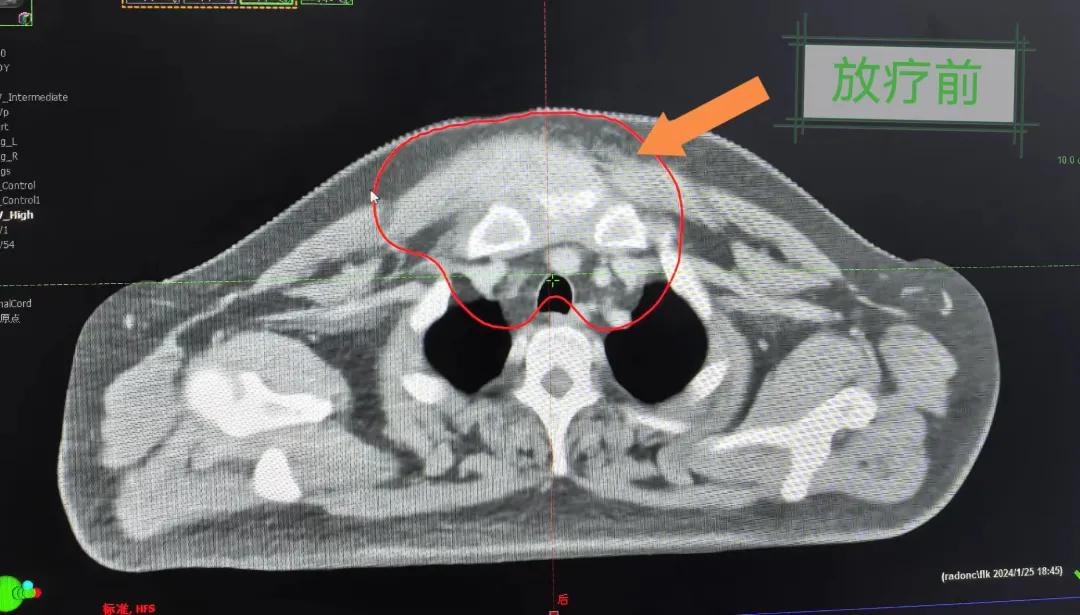

隨后,趙亮主任帶領(lǐng)放療團(tuán)隊以最快的速度完成了患者的放射治療計劃,在保證放療精準(zhǔn)打擊腫瘤的同時,利用先進(jìn)的三維立體精確放療技術(shù),最大限度的避免心臟、肺部的損傷發(fā)生,整體治療精準(zhǔn)度達(dá)到1mm以內(nèi)。經(jīng)過10次的放射治療后,患者疼痛已明顯減輕,胸部腫物肉眼可見的縮小,患者及家屬臉上終于露出久違的笑臉。

治療期間,患者沒有出現(xiàn)明顯不適,治療結(jié)束后,患者胸壁腫物由最初8cm縮小至約1cm,后患者至外科行手術(shù)治療。